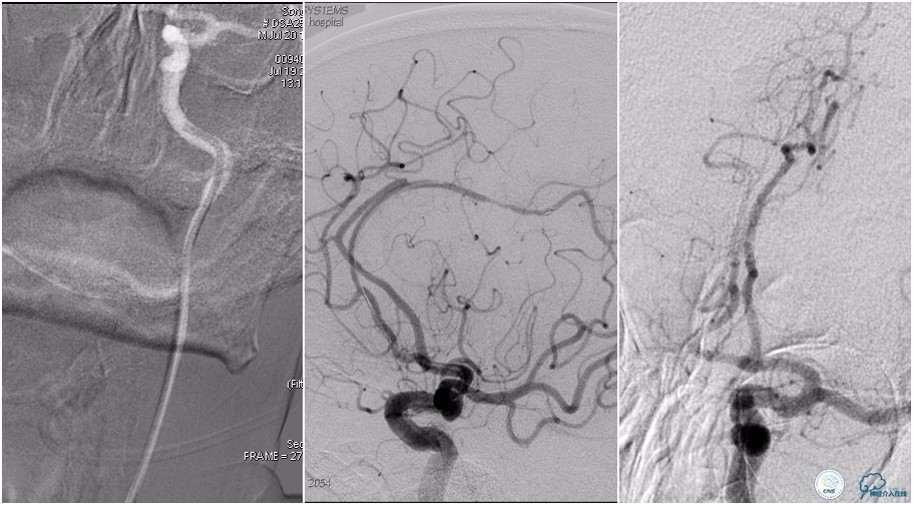

12:35穿刺成功,TOT 185min。3型主动脉弓,右侧颈内动脉起始部狭窄70%,右侧大脑前动脉A1段未显影。

双侧大脑前动脉A4段闭塞,右侧大脑前动脉由左侧大脑前动脉经前交通动脉代偿供血。

6F Envoy置于颈内动脉C3段,选用Solitaire-FR 4*20mm支架释放于右侧大脑前动脉,完全覆盖血栓。